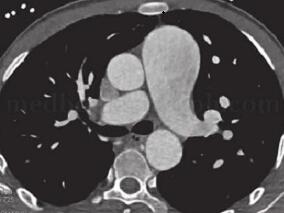

1小时条评论肺动脉异常起源于升主动脉(AOPA),是一种少见先天性肺血管畸形,该疾病的表现与其他常见大量左向右分流的先心病类似,无特异性症状和体征;因发病率低,所以常被忽视而漏诊、误诊。下面是2例这样的疾病 【临床资料】 例1 患者,男,28岁。活动后胸闷气短2年。 ...